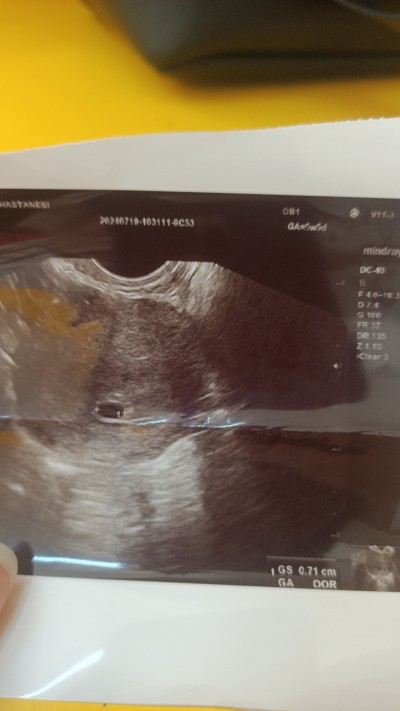

Merhabalar geçen hafta cuma doktora gittim adetime gore 5+5 olması gerekiyor doktor karından ultrason ile göremedi vajinal ultrason ile görebildik ama kese haftasına göre küçük dedi geç döllenme olmuş dedi kesenin ölçüsunu kac hafta ile uyumlu olduğunu söylemedi aklım çok karışık acaba sağlıksız gebelikmi ultrason görüntüsü bu bilen varsa bi yardımcı olsun

adın gibi pimririkli olma, geç döllenme normal bir durum. önemli olan kesenin düzgün gelişmesi bebek ve kalp atışı olması. onlar da 1 hafta sonra olur